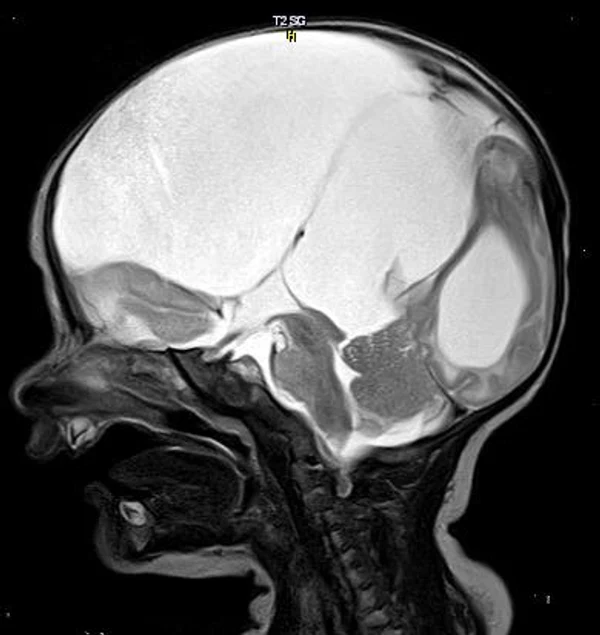

кисты, аномалии Денди-Уокера и др.Операции при внутричерепных кистах. В основном встречаются арахноидальные кисты различных локализаций и кисты сосудистых сплетений боковых желудочков. Пациентам с врождёнными кистами операции проводятся в следующих ситуациях: увеличении объема кисты в динамике, наличии клинических проявлений, компрессии и дислокации мозговых структур, наличии окклюзии ликворных путей. Нами используются 2 способа хирургического лечения кист: эндоскопическая перфорация стенок кист и открытая резекция кист. Открытая резекция кист проводится при ретроцеребеллярных арахноидальных кистах (рис. 2), при арахноидальных кистах межполушарной щели при отсутствии непосредственного контакта их стенок со стенками расширенных желудочков головного мозга и повторного увеличения кист средней черепной ямки после эндоскопической кисто-цистерностомии. Техника операции заключается в проведение краниотомии и максимальном иссечении стенок кист с созданием широкого сообщения кист с субарахноидальным пространством. Эндоскопические операции проводятся при арахноидальных кистах межножковой и пинеальной цистерн, арахноидальных кистах межполушарной щели при тесном контакте их стенок со стенками расширенной желудочковой системы (рис. 3), первично при арахноидальных кистах средней черепной ямки, а также при кистах сосудистых сплетений боковых желудочков. При арахноидальных кистах межножковой цистерны эндоскопически проводится перфорация стенок кисты, сообщая ее с просветом III желудочка и межножковой цистерной – эндоскопическая вентрикуло-кисто-цистерностомия (рис. 4). При арахноидальных кистах пинеальной цистерны проводится перфорация кисты в передне-верхних её отделах с созданием сообщения полости кисты с просветом III желудочка – эндоскопическая кисто-вентрикулостомия. С целью предотвращения облитерации сформированного отверстия иногда в полость кисты под контролем эндоскопа вводится стент перфорированный на протяжении (рис. 5, 6). Эндоскопическая кисто-цистерностомия выполняется при арахноидальных кистах средней черепной ямки. При этом создается широкое сообщение кисты с базальными цистернами. При кистах сосудистых сплетений боковых желудочков проводится их вскрытие в просвет боковых желудочков – эндоскопическая кисто-вентрикулостомия. При множественных кистах проводится их хирургическое сообщение между собой – интеркистосмия